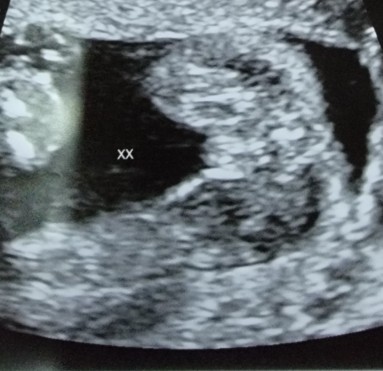

Is this a girl ultrasound at 20 weeks? Just to confirm and reassure

Your ultrasound does look like a girl, but if you want to really confirm again, maybe check with your gynae? Mine looks like this. (like yours) But during my detailed scan at week 20, sonographer double confirmed gender with me.

Yup. XX = girl